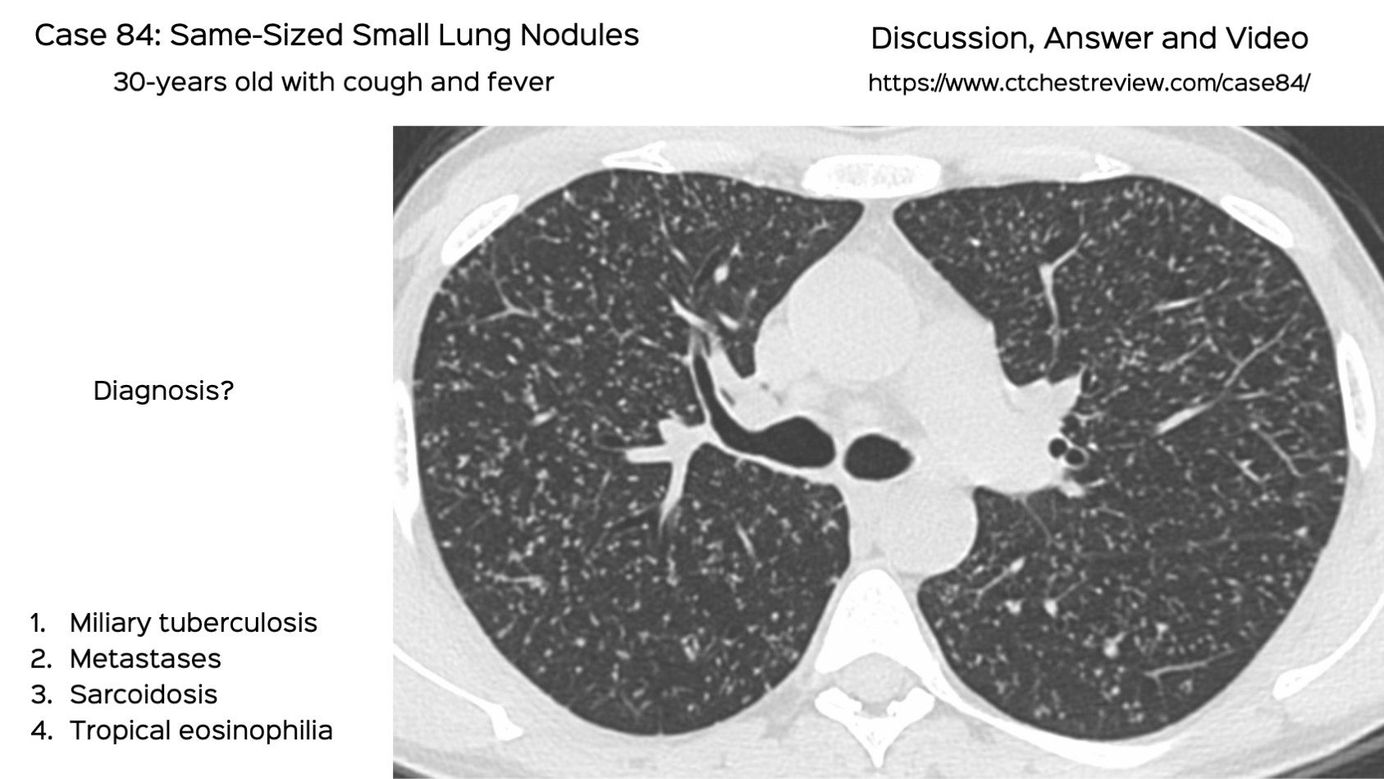

Case 84: Same Sized Small Lung Nodules Members Public

30-years old with cough and fever